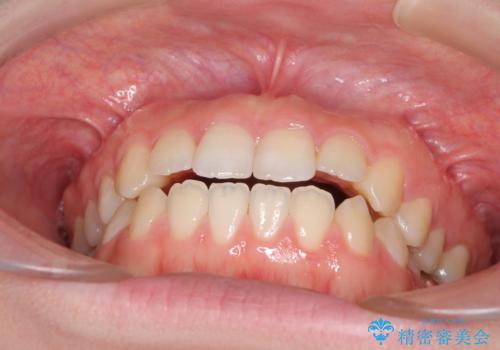

- 口元の膨らみが気になるとのことで来院された患者様です。

非抜歯で口元の突出感を少し改善させる治療も提案しましたが、最大限口元を引っ込めたいとのことでした。

上下左右第一小臼歯4本を抜歯し、ワイヤー装置により矯正治療を行うこととしました。

治療は順調に進み、予定された期間で終了することができました。

装置除去後には、スッキリとした口元となり、大変満足していただきました。